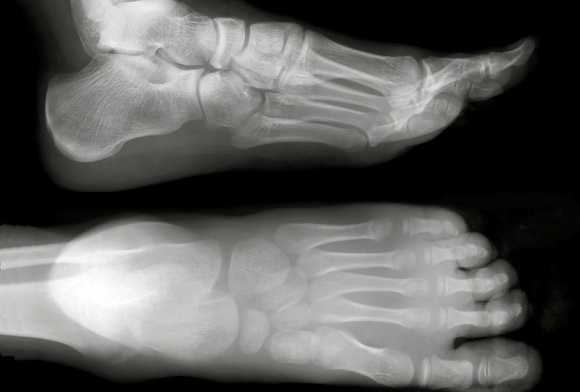

Информативность снимка. На снимке стопы в боковой проекции хорошо видны кости предплюсны: пяточная, таранная, ладьевидная, кубовидная и клиновидная. Кости плюсны проекционно наслаиваются друг на друга. Из всех костей наиболее отчетливо видна V плюсневая кость (рис. 446). На снимках стопы могут быть выявлены различные травматические, воспалительные и опухолевые поражения костей.

Изменения мягких тканей особенно наглядно видны на электро-рентгенограммах (рис. 447, а, б).